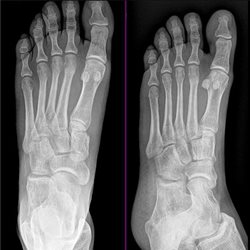

Adult Extremities 5

Various foot cases